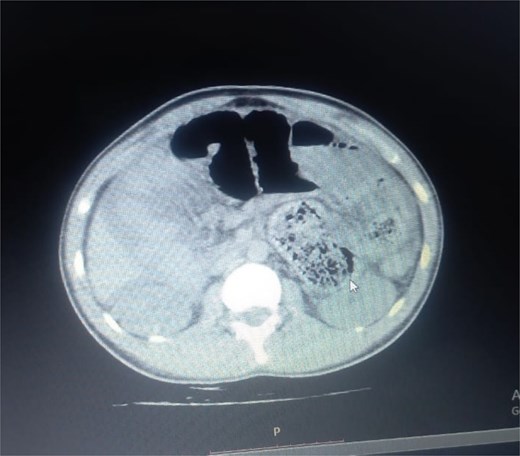

Initial radiographic evaluation with a plain abdominal X-ray confirmed the clinical suspicion of acute intestinal obstruction, demonstrating multiple air-fluid levels and diffuse small bowel dilatation (Fig. 1). To further delineate the underlying etiology, a contrast-enhanced computed tomography (CECT) scan was performed; providing critical diagnostic information it revealed, in the right iliac fossa, a striking encapsulation of the small intestine loops within a sac-like membrane, accompanied by ascites. This constellation of findings formed a pathognomonic cocoon-like structure (Fig. 2). Furthermore, the CECT identified a concurrent gut malrotation, evidenced by a left-sided displacement of the colon (Fig. 3). Laboratory findings showed an elevated total leukocyte count (TLC) of 21 000, indicative of inflammation, while other parameters were within normal limits. The patient underwent an exploratory laparotomy. Intraoperatively, the abdominal viscera were encased within a thick fibrous membrane (Fig. 4), containing ascitic fluid. The membrane was incised, adhesiolysis was performed, and the entrapped small bowel loops were released, and then a kink in the small intestine causing obstruction was identified and corrected. Additionally, the appendix was found to be secondarily involved in the encapsulating process. It was encased in the dense fibrocollagenous membrane, forming an inflammatory mass consistent with chronic serositis and localized fibrosis, rather than a classic acute appendicular phlegmon. Based on this intraoperative assessment that the mass was a manifestation of the cocoon’s chronic inflammation, a simple appendectomy was performed instead of a more extensive right hemicolectomy. This procedure was necessary to achieve complete release of the entrapped bowel, remove this localized inflammatory focus, and obtain a specimen for histopathology to definitively rule out a primary appendiceal pathology as a secondary cause of the peritonitis. Furthermore, ascitic fluid analysis showed no bacterial or mycobacterial growth, ruling out tuberculosis and the histopathological examination confirmed the fibrocollagenous nature of the membrane. The patient recovered well postoperatively and was discharged on the sixth day with advice for a follow-up after 2 weeks. At the follow-up visit, he reported no symptoms, and abdominal imaging confirmed the absence of obstruction. Histology further confirmed the benign fibrous nature of the membrane, with no signs of malignancy.

Axial CT demonstrating key pathological features. This contrast-enhanced axial view shows the colon displaced to the left side of the abdomen, confirming the presence of gut malrotation. The centrally clustered small bowel loops are seen encased in a dense sac, forming the characteristic cocoon structure that is pathognomonic for abdominal cocoon syndrome.